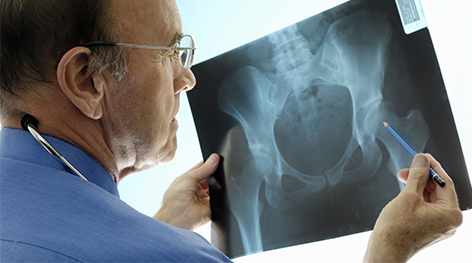

Haciendo una medición de la densidad mineral ósea. Esta es una prueba que suele realizarse a personas que presentan factores de riesgo de osteoporosis.